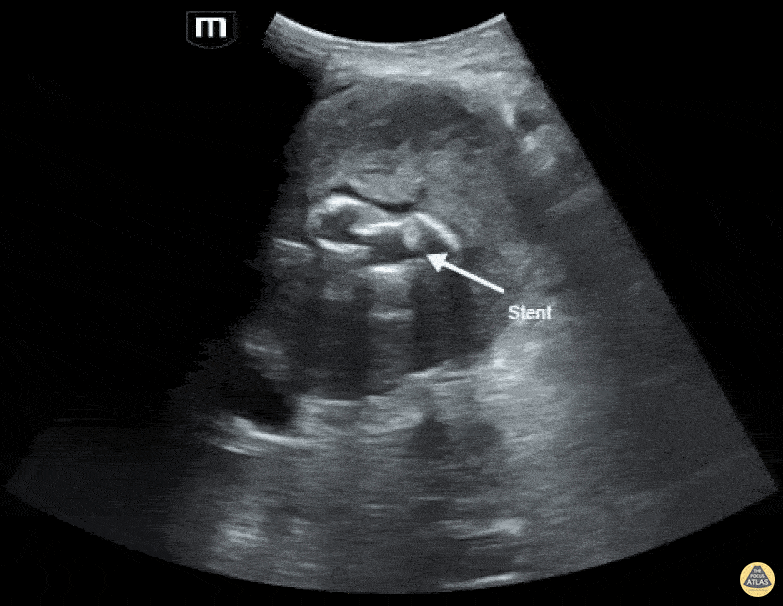

A patient in their 80s with PMH of abdominal aortic aneurysm s/p grafting with type 2 endoleak presented to the ED for dizziness. Bedside ultrasound demonstrated an 8.55 cm aortic aneurism with large thrombus. Endoleak is the hypoechoic area seen above the hyperechoic endograft. Mehtab Galeh, MD; Bayley Espinoza, MD